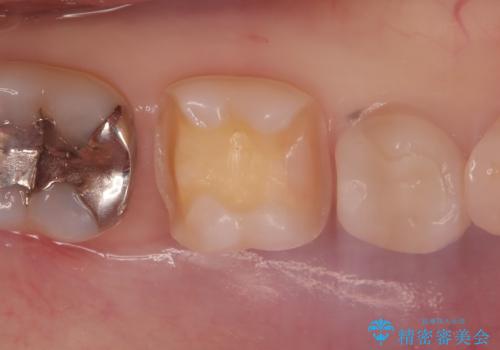

- 主訴:下の歯に入っている銀歯が笑うと目立つので白くしたい。

下顎臼歯部に入っている保険適用のメタルインレー(4箇所)を、審美性・適合性・清掃性の良いセラミックインレーにてやり替えました。